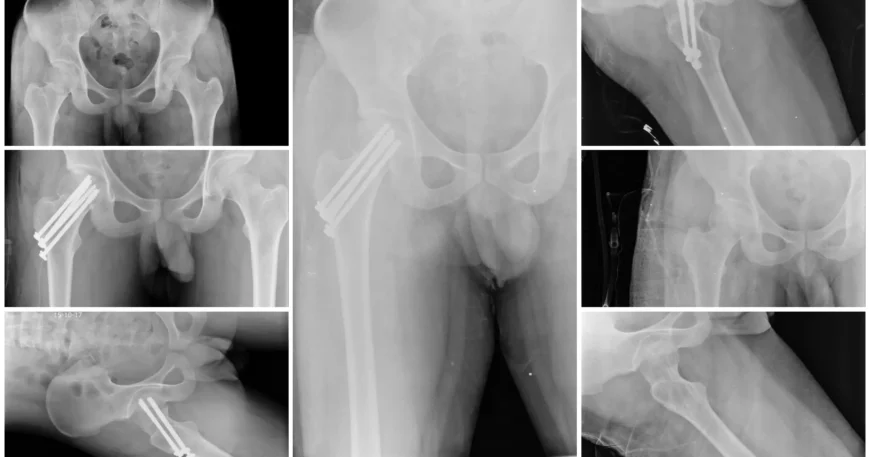

Right Femur Neck Fracture Treated with Closed Reduction and Internal Fixation Using CC Screws | Balanku Hospital

Clinical examination and imaging studies confirmed a Right Femur Neck Fracture, a fracture occurring just below the ball of the hip joint.

Closed Reduction and Internal Fixation (CRIF) with CC Screws

Mr. Naga Santhosh underwent Closed Reduction and Internal Fixation (CRIF) using CC (Cannulated Cancellous) Screws.

The procedure was performed with precision under imaging guidance to ensure accurate screw placement and optimal stability.